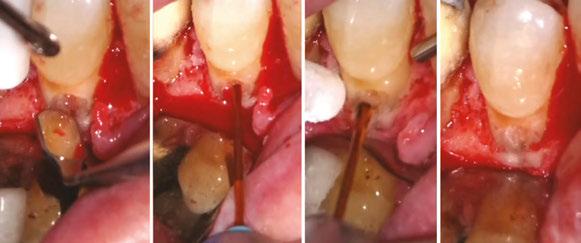

on the crest of the ridge in the region of teeth Nos. 15-25. While creating the incision, bleeding was noticed in the region of tooth No. 15 which intensified during the flap reflection (Figure 2). Bleeding was pulsatile, indicating an arterial bleed. Initially attempts to control bleeding included a pressure pack and ice pack, and the bleeder was isolated, and the vessel ligated (Figure 3). The bleeding could be controlled, and the procedure was completed by placing four Bioner implants (Bioner, Spain), size 4/10 mm. Sutures were placed, and patient was kept on basic medication for pain and infection control. Immediately after the surgery, the patient was advised to get a CBCT. As shown in Figure 4, a coronal view and Figure 4B (yellow arrows), the position of the artery can be seen.

Figure 1: Pre-op panoramic radiograph Figure 2 (left): Alveolar antral artery (AAA). Figure 3 (center): The artery has been ligated with suture. Figures 4A and 4B (right): CBCT post-implant placement and position of the artery coronally (top). 4B. Showing the position of alveolar antral artery (AAA) in relation to implant placement as indicated by the yellow arrows (bottom)